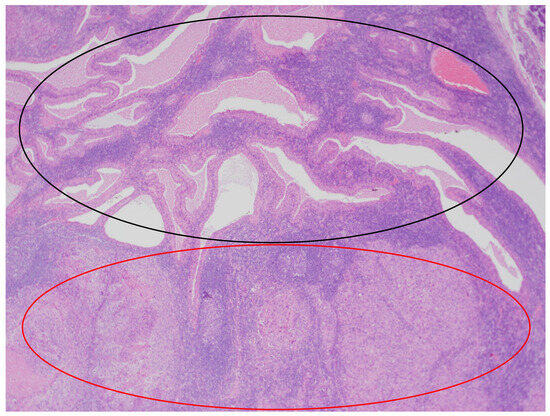

Figure 3.

The parotid Warthin tumor, with the benign epithelial cystic component in the superior part of the photo (black circle) and squamous cell carcinoma metastasis in the inferior part (red circle). HE staining. Magn. ×88.